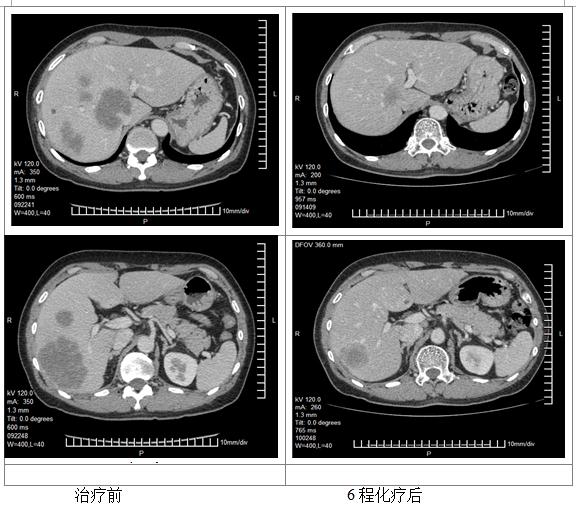

更改化疗方案: FOLFIRI+ bevacizumab 4次

评估:PR

手术治疗

手术名称:右半结肠切除+右半肝切除术

术后2月复查

复发时间:2016.2

2程化疗后展示的患者肝脏CT无明显改变,评价为PD的原因不明。若患者因肝脏或其他部位出现新发病灶出现了病情进展,可考虑二线采用FOLFIRI联合贝伐单抗,4程化疗后肝脏病灶明显减少、缩小,评价为PR。因贝伐单抗使用后需暂停6周以上才能进行手术,因治疗间隔太长,建议该患者在停用贝伐单抗期间进行FOLFIRI方案化疗2至3疗程。手术切除原发灶和肝转移灶,病理已确认。其后患者进行了术后辅助化疗4程,患者术前行化疗4程,仅出现Ⅱ度骨髓抑制,根据NCCN指南术后可建议其行8程FOLFIRI方案或2-3程FOLFIRI方案加6-5程FOLFIRI联合贝伐单抗方案化疗,达到共6个月的围手术期化疗。

一线治疗以肿瘤退缩为目的争取手术根治机会应推荐有效率更高的方案;二线治疗取得有效后停药时间过长应在停用贝伐单抗准备手术的基础上再行化疗两到三程;化疗配合根治性手术达到无疾病证据(NED)状态,围手术期化疗建议能达到半年时间;患者出现疾病复发后建议更加积极地进行多学科讨论采取多学科联合的方案。

此病例患者首先因为发现肝占位入院,完善检查,诊断升结肠癌 肝转移,原发证升结肠肿瘤可手术切除,但肝内病灶多发(6个),尤其侵犯门静脉主干分叉处,该病例不能归于寡转移疾病。经过MDT会诊,转移灶初治时不可切除,暂无R0手术切除可能,鉴于原发升结肠病灶没有梗阻、出血等症状,一致建议选择转化化疗,降期争取手术治疗是其目的。依据ESMO分组意见,该病例属于组1患者。尽管是一线转化化疗效果欠佳,但是bevacizumab联合FOLFIRI的化疗获得了明显的PR效果,转化为可切除。这个病例显示出如果治疗目标是从不可切除转化为可切除,bevacizumab联合化疗还是有较好的肿瘤退缩效果。该患者总体生存达2年以上,整体治疗是成功的,MDT讨论决策至关重要。但术前评估、手术时机的选择、以及靶向用药等也存在一些需要进一步讨论的问题。

患者肝内发现6个病灶,位于右肝,有一个大肿瘤临近门静脉主干,K-RAS为突变型,术前的转化化疗有一个PR的良好反应,所以这个患者的治疗目标还是应该是治愈。所以,治疗选择一定是根治性的治疗。由于肿瘤靠近门静脉主干,手术中外科医生做了最大努力使得病灶达到肉眼R0切除,实属不易。但术后半年不到时间出现复发,是否与未采用磁共振评估肝转移灶有关,值得商榷。最近韩国有一项多中心回顾研究提示对于临床完全缓解的肠癌肝转移患者,普美显-磁共振漏诊率明显低于增强CT(22.0% vs. 64.8%)。因此,还是要强调肝脏转移瘤常规行磁共振检查。